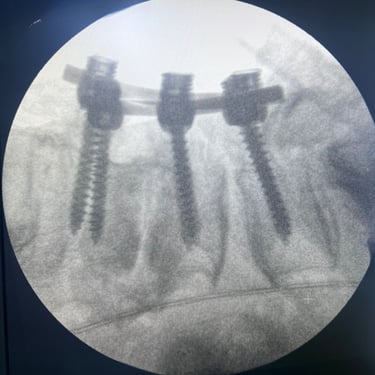

🧠 Artrodesis Posterior | TLIF Abierto.

El TLIF abierto es una técnica de artrodesis lumbar posterior que combina descompresión y fusión intersomática. Mediante resección discal y colocación de injerto con caja intersomática, más tornillos pediculares, se estabilizan las vértebras y se descomprimen nervios. Permite aliviar dolor y mejorar la función del paciente.